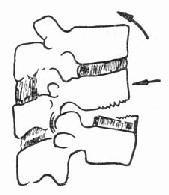

(一)压缩骨折 前屈或侧屈暴力引起,最常见的为椎体前缘高度减少的前方楔伏骨折(图73-1)。此外还有侧方压缩骨折,即椎体两侧高度不一样。这些楔伏改变常伴有椎体终板的损伤及椎间盘的损伤,椎间盘可被压进椎体内。但压缩骨折的椎体后缘高度不变,有别于爆裂型骨折。

图73-1 前方压缩骨折